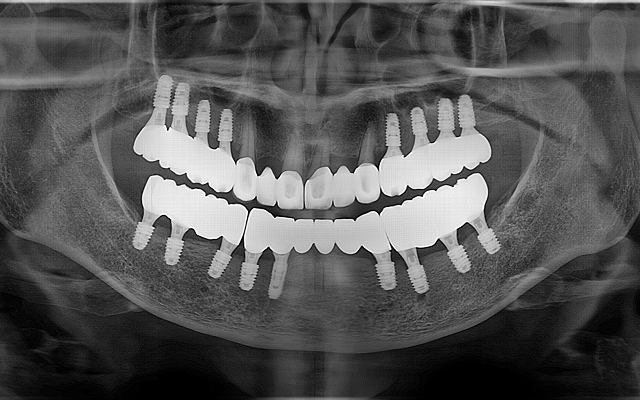

교합거상 케이스

- 마모·손상으로 낮아진 물림 높이를 정밀 분석 후 단계적으로 회복

- 턱관절·저작근 균형을 고려하여 기능과 심미를 동시에 개선